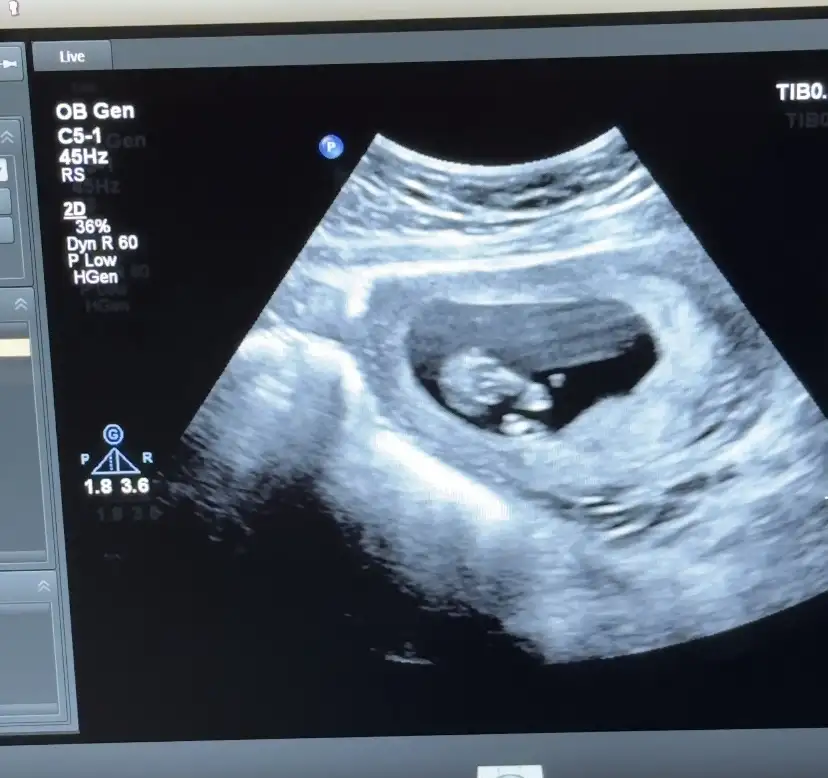

Kızlar öncelikle sağlıkla gelsin bebişlerimiz. Ben cinsiyetle alakalı bir şey sormak istiyorum. Baştan beri kız hissediyorum ilk bebegim ve 3 kez rüyamda kız gördüm. Hatta üçüncüsü çok netti suratını bile çizebilirim. Ama iki doktora gittim ikisi de erkek dedi 13-14. Haftada falandık sanırım. Şuan 16 olmak üzere. Acaba yanılma ihtimalleri var mı ben hala kız oldugunu hissediyorum rüyalardan dolayı kafam çok karışık.

Yanılma olabilir canım ben 12 haftada Medical park Keçiören hastanesinde çok iyi bi doktora gittim ve kesin erkek dediler ama ben hep kız hissediyorum hiç inanmadım 15.ve 17 haftada devlet hastanesine gittim ve bu bebek kız dediler kesinleşti kız olduğu Allah gönlüne göre versin inşallah